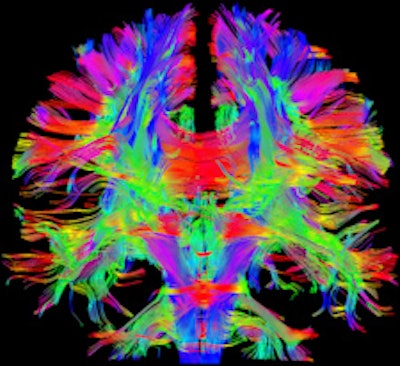

The system also offers a tandem configuration unavailable in any other commercial whole-body system, according to the vendor. The device's combination of high gradient strength and fast gradient switching speed allows for increased image quality compared with conventional devices. Due to this combination of high spatial and temporal resolution, the new machine can reportedly achieve good image quality, especially in very demanding applications. Furthermore, by combining high gradient strength with fast gradient switching speed, the Magnetom Prisma offers new possibilities in areas such as diffusion imaging, because even minor diffusion effects can be captured. Moreover, the diffusion spectrum imaging (DSI) application makes it possible to resolve fine anatomical details of the brain, such as crossing white-matter fibers by using up to 514 diffusion encoding directions, Siemens stated.